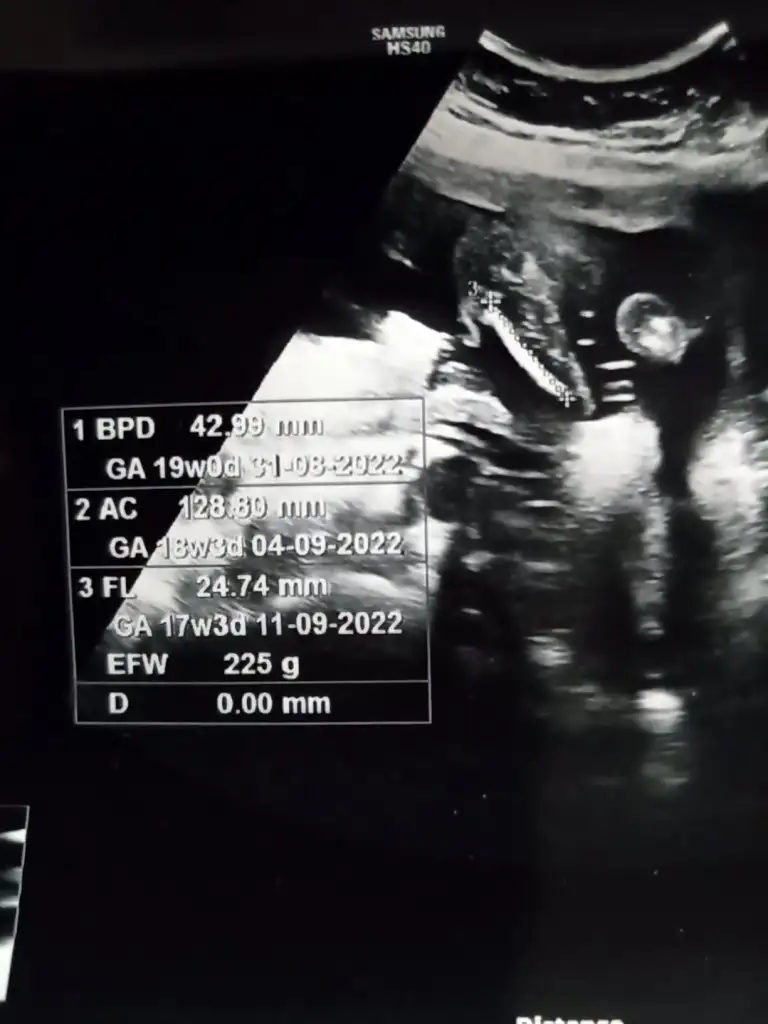

Kızlar bebeğin boyu kilosu nerede yazıyor acaba bakar misiniz .bugun kontrolum vardida iyimi kilosu nerden anlayacağım